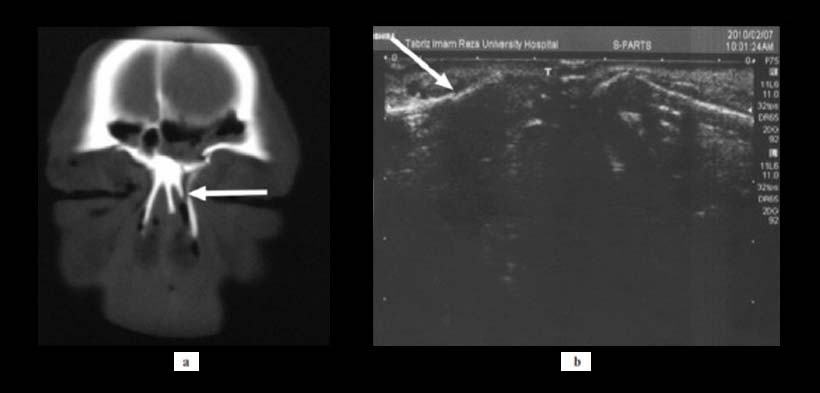

Fig. 2. Una mujer de 40 años con fractura de hueso nasal unilateral (flechas blancas). (a) vista CT y (b) Ecografía que detecta la fractura del hueso nasal.